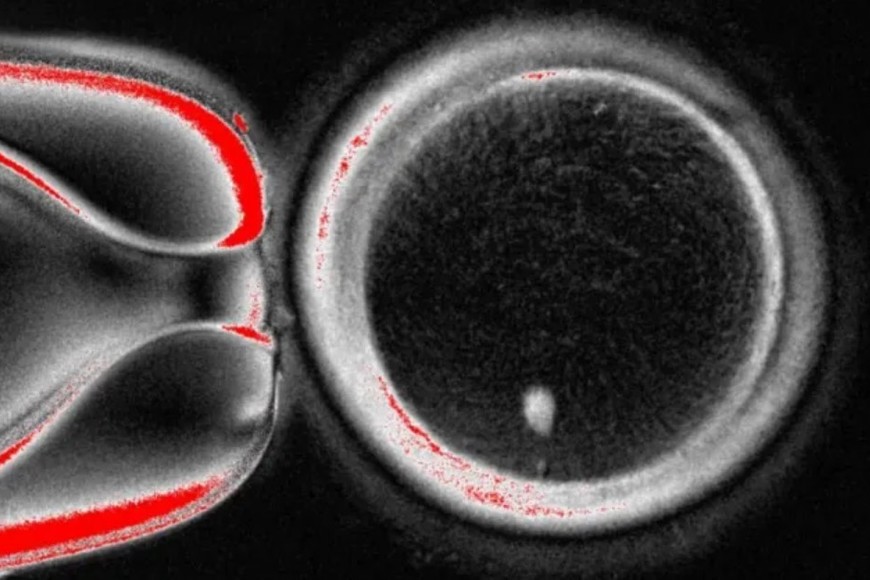

La técnica del equipo de investigación de la Universidad de Salud y Ciencias de Oregón extrae el núcleo (que alberga una copia de todo el código genético necesario para construir el cuerpo) de una célula de la piel. Luego se coloca dentro de un óvulo de donante al que se le han quitado sus instrucciones genéticas.

Hasta ahora, la técnica es similar a la utilizada para crear a la oveja Dolly, el primer mamífero clonado del mundo, nacido en 1996. Sin embargo, este óvulo no está listo para ser fertilizado por un espermatozoide porque ya contiene un conjunto completo de cromosomas.

El humano herda 23 de estos paquetes de ADN de cada uno de sus padres, para un total de 46, que el óvulo ya tiene. El siguiente paso es persuadir al óvulo para que descarte la mitad de sus cromosomas en un proceso que los investigadores han denominado "mitomeiosis" (la palabra es una fusión de mitosis y meiosis, las dos formas en que las células se dividen).

El estudio, publicado en la revista Nature Communications , mostró que se formaron 82 óvulos funcionales. Estos fueron fecundados con espermatozoides y algunos alcanzaron las primeras etapas del desarrollo embrionario. Ninguno superó los seis días de desarrollo.

La técnica está lejos de ser refinada, ya que el óvulo elige aleatoriamente qué cromosomas descartar. Necesita tener uno de cada uno de los 23 tipos para prevenir enfermedades, pero termina con dos de algunos y ninguno de otros. También hay una tasa de éxito baja (alrededor del 9%) y los cromosomas pierden un proceso importante en el que reorganizan su ADN, llamado entrecruzamiento.